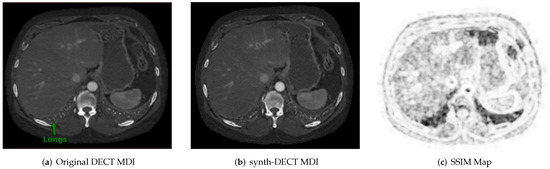

Figure 3. Example cross sectional axial slices from the test dataset used for Pix2Pix. (a) The original dual energy CT material density iodine (DECT MDI). (b) The synth-DECT MDI for the slice shown in (a). The global structural similarity index (SSIM) for the scan from which the slices were taken was computed to be 0.92. (c) This figure displays the local SSIM scores for each pixel of the slices in (a,b) as an image: The dark areas depict small values of the SSIM, which indicates a large difference between the original and synthetic image. The bright regions show large values of the SSIM or areas that were the most similar between the original and synthetic.

Across the nine test set scans, the average SSIM was computed as 0.94 ± 0.014 . Figure 3a,b shows an example cross-sectional axial slice from a single patient CT scan in the Pix2Pix test set. Subjectively, the original and synthetic slices in Figure 3a,b appear similar, but upon closer inspection, the base of the lung field pointed at in Figure 3a was blurred in the synthetic slice. Similar blurring in the lung field was observed across all test set scans. Figure 3c displays the local pixel level SSIM values computed between the slices shown in Figure 3a,b. The darker portions in Figure 3c point to air-filled cavities where the computed SSIM decreased. One reason for the low local SSIM within the air-filled cavities is that the effective attenuation of air within the lungs is neither similar to the two basis pairs, water or iodine, which were used to reconstruct the DECT image types. When the effective attenuation is unlike the two basis materials, a negative pixel value is assigned in the original DECT MDI scan.